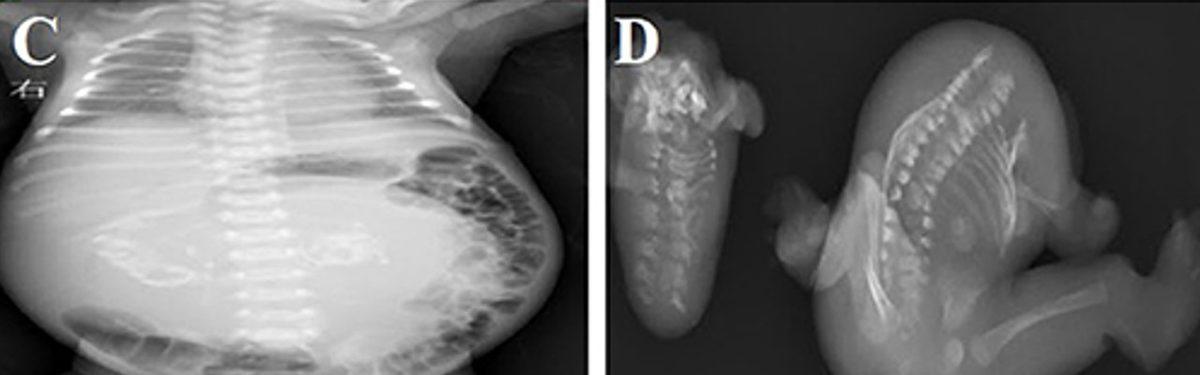

Bu sendromu gösteren fetüsün muayene esnasında karnı şiş, aynı zamanda yumuşaktı ve karnındaki kitleler belirgin bir şekilde ele geliyordu. Kitle fetüs görünümünde, uzuv benzeri yapılara, anormal iskelet ve bağırsak gelişime sahipti.

Olguların yaklaşık %80'inde bu anormal durum, normal fetüsün vücudunda karnın arka bölgesinde ortaya çıkıyor ancak göğüs, kasık ve kuyruk sokumu gibi vücudun diğer bölgelerinde de görülebiliyor.

Tanı ve tedavi için ise fetüs içinde yeni bir fetüs oluşumuna sebebiyet veren bu kitle, yeni doğan bebeklerin vücutlarına potansiyel olarak zarar verirken, ameliyatla çıkarılmalı ve incelenmelidir.